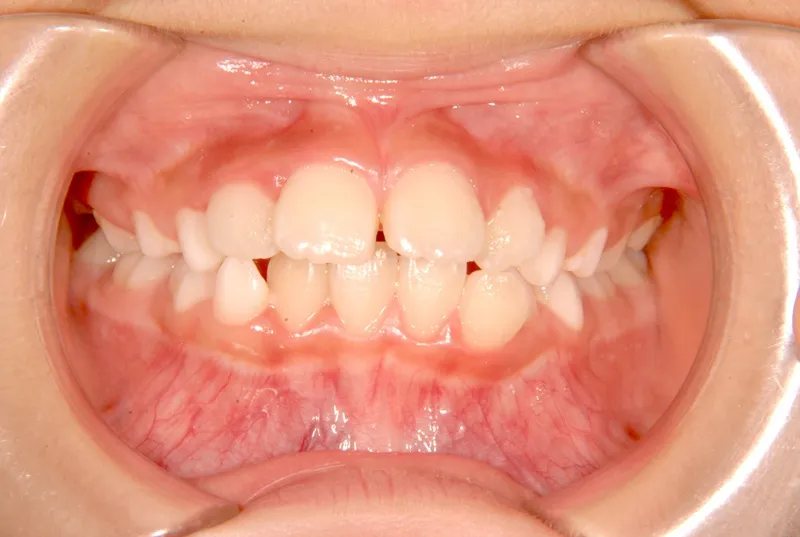

• 初診

初診時年齢 小学校3年生 (女性) 主訴 出っ歯・前歯がゆがんでいる

診断名 叢生・上顎前突 装置名

状態 永久歯が生える隙間がない(叢生)

ガタガタ・でこぼこに生えている(叢生)

出っ歯(口元が出ている/上顎前突)

初診